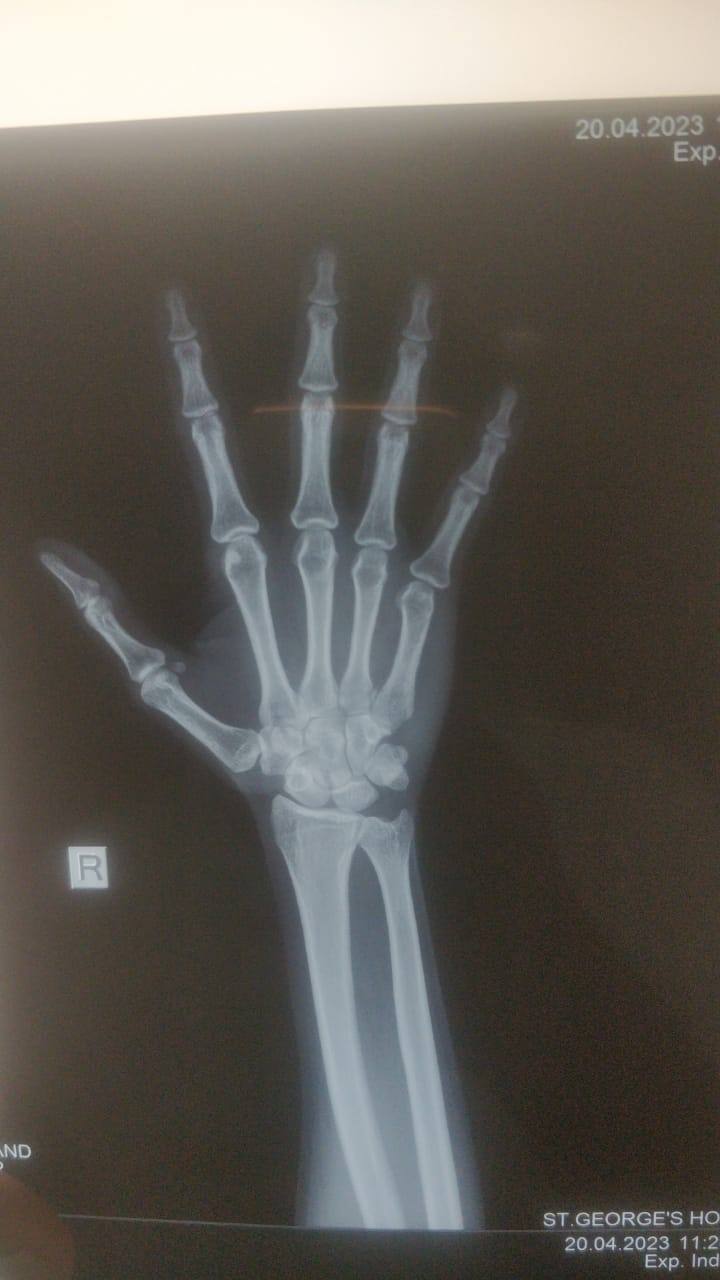

5th metacarpal hair line fracture Required surgery or not? Because doctor suggest me for surgery please reply as soon as possible sir.

5th metacarpal hair line fracture Required surgery or not ??